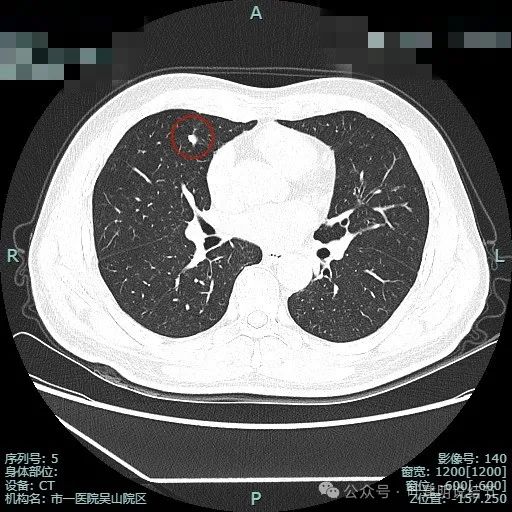

先来看两肺多发结节的总体情况:

病灶1:左上叶肺尖淡磨玻璃影,轮廓稍显模糊,少许慢性炎或肺泡间隔增宽可能性大。

病灶2:右上肺胸膜下微小磨玻璃结节,表面欠光滑,倾向肺泡上皮增生之类的病变,目前不十分确切,但风险总是低的。

病灶3:右上叶点状偏高密度微小结节,只有1毫米许,无法定性,但增殖灶的可能性大点,因为密度感觉稍显高。

病灶4:左上叶点状高密度结节,良性可能性较大。

病灶5:右上叶前段血管旁微小磨玻璃结节,轮廓较清,与血管挨得近,考虑是肺泡上皮增生或不典型增生可能性大。

病灶6:右上叶后段磨玻璃结节,有浅分叶征,结合前面图上有血管穿行,考虑是肿瘤范畴的,以微浸润性腺癌或浸润性腺癌贴壁为主型可能性大。

病灶7:左上叶胸膜下微小不足1毫米点状高密度,无法定性,但良性可能性大,因为密度显得较高;

病灶8:距离胸膜约1.5厘米许微小磨玻璃结节,大概1-2毫米之间,轮廓较清,以肺泡上皮增生可能性较大;

病灶9:左上叶胸膜下微小结节,密度不如病灶7高,又不如病灶8大,无法确定性质,但必能随访。

病灶10:右上叶胸膜下微小结节,表面不平,密度也非实性,显得形态不太规则,考虑良性或肿瘤范畴的原位癌或微浸润性腺癌均可能,但太小了,如果只有此灶只需随访。

病灶11:右肺实性结节,边缘略模糊,缺乏膨胀感,考虑良性可能性大些。

病灶12:右下叶微小结节,点状,密度较高,良性增殖灶可能性大。

病灶13:左上叶舌段磨玻璃结节,但呈长条状,贴着胸膜,纤维条索可能性稍大,但由于密度不够高,也无法完全除外肿瘤范畴的肺泡上皮增生或不典型增生,但必能随访。

病灶14:左上叶微小结节,密度较高,但未钙化,考虑增殖灶可能性大。